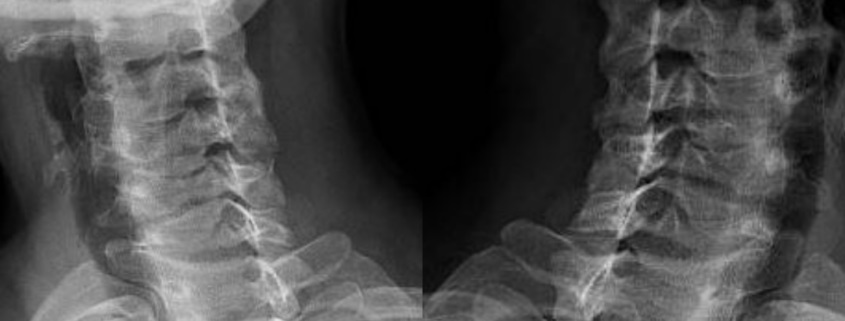

Se le llama lordosis cervical a la curvatura que se forma en la columna, específicamente hacia adelante. La columna está compuesta por las vértebras, las cuales (a pesar de que no lo parezca) no tienen una estructura recta. En realidad la columna está compuesta por dos curvas: lordosis y cifosis, las cuales diariamente se encargan de soportar todo el peso del cuerpo.

- La lordosis normal es cuando la columna cuenta con curvas.

- En cambio la hiperlordosis se produce cuando las curvas de la columna se acentúan más de lo normal. La hiperlordosis lumbar suele ser bastante dolorosa.

- Por otro lado la rectificación lumbar es la pérdida de las curvas normales de la columna. Como resultado de esto la persona afectada puede sentir mucho dolor o tener una postura arqueada. Esta afección suele ser bastante común durante el embarazo o al padecer problemas de sobrepeso.

- La inversión de arco cervical se produce cuando la rectificación lumbar evoluciona.